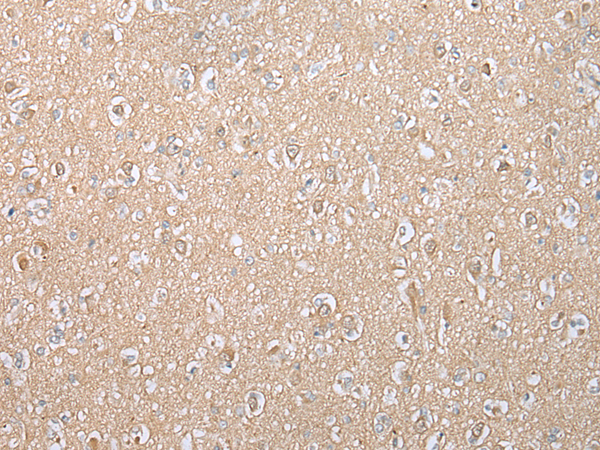

分类: 科研抗体货号: P02100别名:应用: WB,IHC反应种属: Human, Mouse

分类: 科研抗体货号: P02020别名: Ipi3; R32184_1应用: WB,IHC反应种属: Human, Mouse

分类: 科研抗体货号: P01920别名: HAT应用: WB,IHC反应种属: Human, Rat

分类: 科研抗体货号: P02094别名: EMC5; TMEM32应用: WB,IHC反应种属: Human, Mouse, Rat

分类: 科研抗体货号: P01915别名: CAPH2; MT-SP2; TMPRSS3应用: WB,IHC反应种属: Human, Mouse

分类: 科研抗体货号: P02005别名:应用: WB,IHC反应种属: Human, Mouse, Rat

分类: 科研抗体货号: P02092别名: NAAGS; FAM80B; NAAGS-I应用: IHC反应种属: Human, Mouse

分类: 科研抗体货号: P02085别名: ECO; ICK; MRK; LCK2; EJM10应用: IHC反应种属: Human, Mouse, Rat

分类: 科研抗体货号: P02002别名:应用: WB,IHC反应种属: Human, Mouse